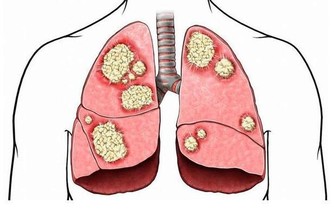

拇指疼痛:拇指中少商經穴與肺息息相關。如肺有疾病,壓這個部位是會會痛得

跳起來。